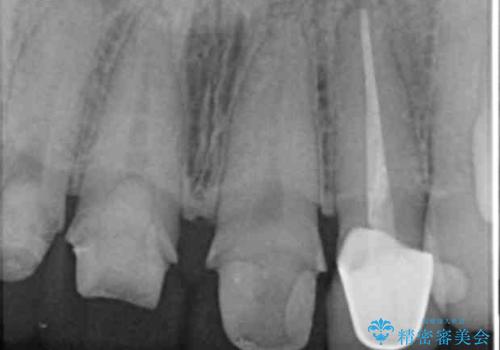

- 前歯を天然の歯のようにきれいにやりかえたいと希望され来院されました。

根尖病変の存在が判明したため、感染根管治療後にオールセラミックジルコニアクラウンを製作します。

- 37万円(仮歯×3・ファイバーコア×2・ジルコニアクラウン×3)費用は治療当時の料金となります